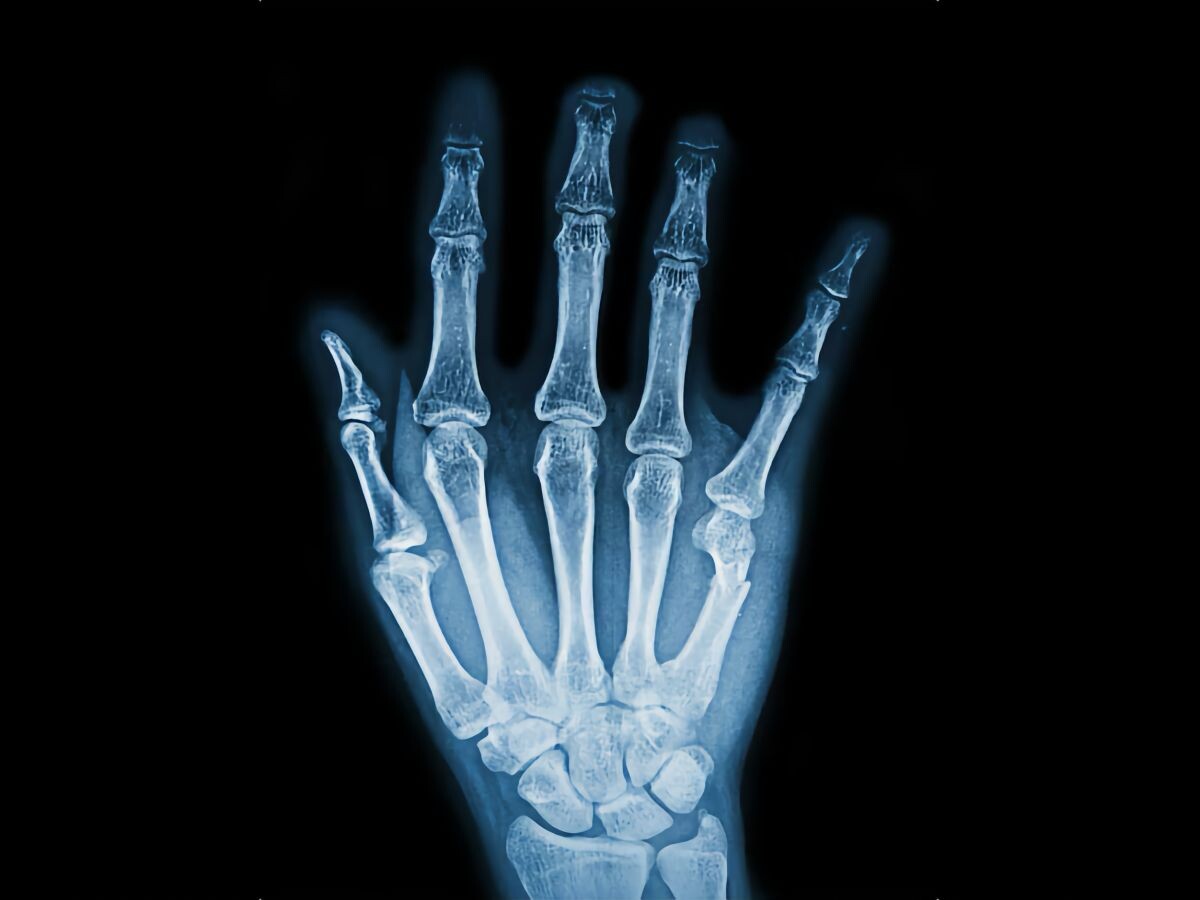

В скором времени хирурги могут получить в своё распоряжение необычный прибор, способный печатать костные импланты прямо во время операции. Разработка обещает сделать ортопедические вмешательства быстрее и безопаснее, снижая риски инфекций и ускоряя заживление переломов.

Технология основана на модифицированном «клеевом пистолете», способном работать при низкой температуре и быть безопасным для живых тканей. Он использует стержни из смеси поликапролактона (PCL) и гидроксиапатита (HA) — минерала, присутствующего в костях.

Такой состав может также содержать антибиотики, например ванкомицин или гентамицин, что снижает риск послеоперационных инфекций. Учёные протестировали материал сначала на клетках мышей и человека, а затем на кроликах с дефектом бедренной кости.

Эксперименты показали, что при добавлении HA материал становился прочнее и эластичнее, медленнее разрушался и лучше поддерживал рост новых костных клеток. В течение 12 недель после операции 3D-печатные импланты обеспечили более естественное и крепкое восстановление кости, чем традиционный костный цемент, без признаков воспалений.